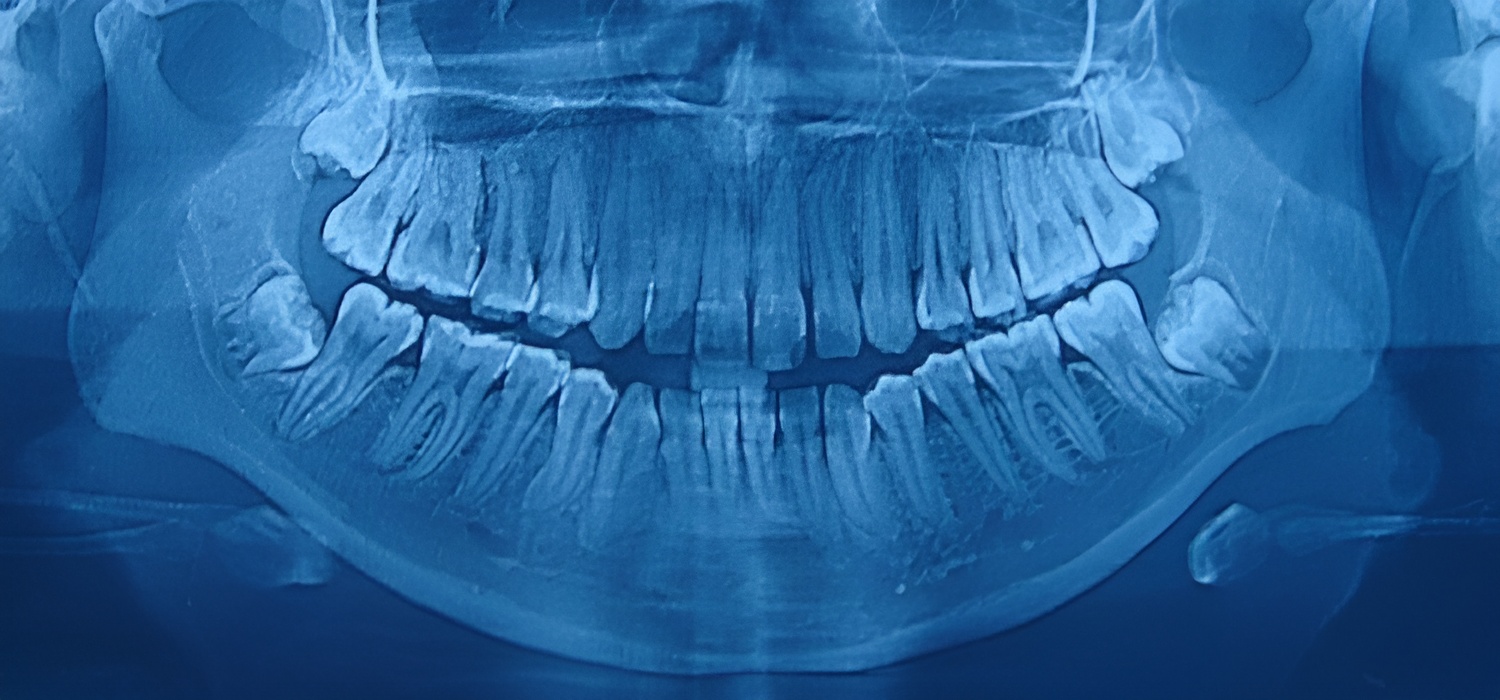

Permite analizar cualquier anomalía presente en los dientes, mandíbula y maxilares, por lo tanto, es de especial utilidad en odontología, cirugía bucal, implantología, ortodoncia o periodoncia. Además de ser útil para fines estéticos y visualizar las estructuras internas, es posible detectar problemas médicos y dentales, tales como:

• Quistes o tumores en la mandíbula

• Detección de deterioro en huesos y dientes

• Presencia y extensión de caries

• Patologías bucales

• Variaciones en senos paranasales

• Dientes impactados

Ejemplo de Imagen informativa